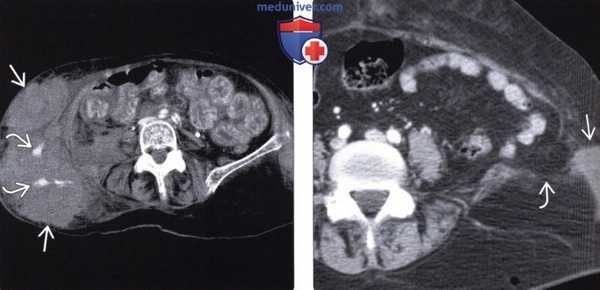

(Слева) На аксиальной КТ с контрастом визуализируются тонкая и ободочная кишка, выбухающие наружу сквозь травматический дефект в брюшной стенке. При операции в некоторых сегментах тонкой кишки были обнаружены разрывы серозной оболочки и ее повреждения отрывного характера, из-за чего потребовалось выполнение резекции.

(Справа) На аксиальной КТ с контрастным усилением определяется травматическая поясничная грыжа с выпадением внутрибрюшной жировой клетчатки, прикрытой только широчайшей мышцей спины. Также обратите внимание на инфильтрацию внутрибрюшной клетчатки возле грыжи. На операции был выявлен разрыв серозной оболочки нисходящей ободочной кишки. (Слева) На аксиальной КТ с контрастным усилением определяются петли тонкой кишки, не усиливающиеся при контрастировании, в большом количестве выбухающие сквозь травматический дефект в брюшной стенке с правой стороны. Определяются также признаки активного артериального кровотечения. Большая часть кишки была обнаружена нежизнеспособной при операции.

(Справа) На аксиальной КТ с контрастным усилением определяется разрыв мышц брюшной стенки в нижних отделах слева, кроме того, мышцы оторваны от места своего прикрепления к гребню подвздошной кости. Обратите внимание на наличие подкожной гематомы в прилежащих отделах. Это - типичный пример повреждений, возникающих при неправильно зафиксированном ремне безопасности.

(Справа) На аксиальной КТ с контрастным усилением определяется травматическая поясничная грыжа с выпадением внутрибрюшной жировой клетчатки, прикрытой только широчайшей мышцей спины. Также обратите внимание на инфильтрацию внутрибрюшной клетчатки возле грыжи. На операции был выявлен разрыв серозной оболочки нисходящей ободочной кишки.

(Слева) На аксиальной КТ с контрастным усилением определяются петли тонкой кишки, не усиливающиеся при контрастировании, в большом количестве выбухающие сквозь травматический дефект в брюшной стенке с правой стороны. Определяются также признаки активного артериального кровотечения. Большая часть кишки была обнаружена нежизнеспособной при операции.